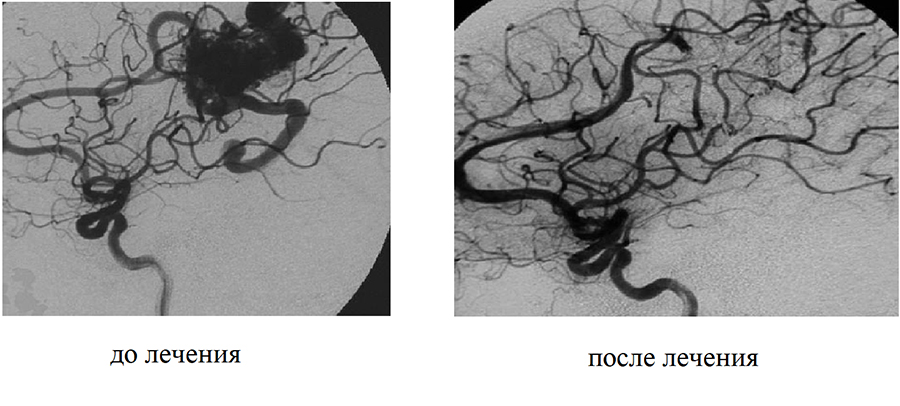

Эмболизаты используют для предотвращения разрыва сосудов, купирования мальформаций (сгустков капиллярных патологических сосудов). Если мальформации находятся в голове, есть риск, что сосуды лопнут, это может привести к внутреннему кровоизлиянию и инсульту. Кроме того, опасны сосуды, в которых происходит отложение холестериновых бляшек, что увеличивает возможность остановки кровотока, приводит к его затруднению.

Наибольшую сложность вызывают операции, связанные с эмболизированием патологий кровеносных сосудов головного мозга. Эти операции проводят с использованием длинных катетеров, которые вводятся в бедренную вену и доходят до патологического разветвления в голове человека. Именно поэтому эмболизат, помимо хорошей контрастности, должен обладать достаточной текучестью и не слишком быстрой скоростью полимеризации.

Синтезом полимера занимались сотрудники лаборатории электрохимически активных соединений и материалов НИОХ СО РАН. Ученые проводили исследования на минипигах в лаборатории экспериментальной хирургии и морфологии Института экспериментальной биологии и медицины НМИЦ им. ак. Е. Н. Мешалкина. Для исследований применялись минипиги селекции ФИЦ «Институт цитологии и генетики СО РАН». Эти животные были выбраны благодаря диаметру сосудов, близкому к человеческому. В испытаниях участвовали эндоваскулярные хирурги и врачи-нейрохирурги, имеющие опыт селективной эмболизации сосудистых мальформаций головного мозга.

«У нас так устроена кровеносная система, что всегда есть обходные пути. Поэтому опасный сосуд можно перекрыть, кровь туда поступать не будет, а пойдет по другим сосудам. Эмболизация — один из самых удобных способов, так как у хирургов не всегда есть возможность провести операцию по удалению мальформаций. Они могут находиться в труднодоступных местах, быть очень маленького размера, или же у человека будут противопоказания к хирургическим вмешательствам», — пояснила Инна Шундрина.